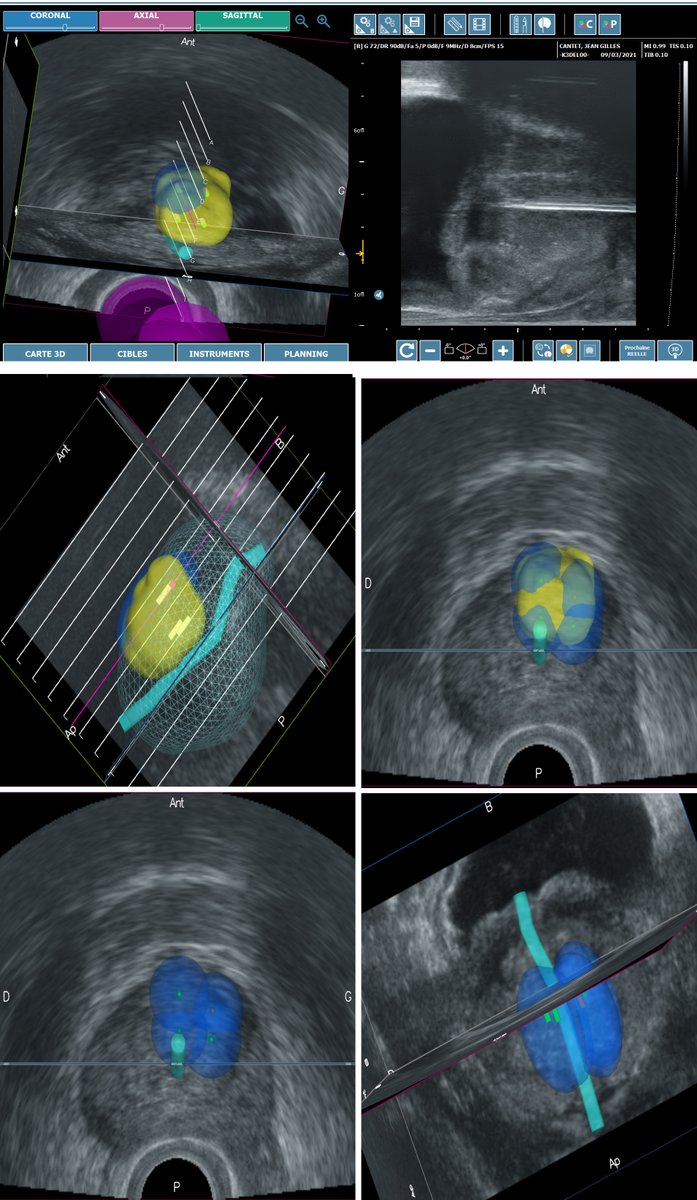

KOELIS Trinity® Perine pour la biopsie transpérinéale de la prostate youtu.be/uvrwM6lsApQ via @YouTube

la @cliniqueuro reste à la pointe de l'innovation et propose le tout nouveau traitement ciblé du cancer de la prostate par micro-ondes guidé par IRM ( @KoelisBx étude de phase 3 multi-centrique européenne )

Mise en place du tout nouveau traitement mini-invasif par micro-onde contre le cancer de la prostate développé par la société francaise @KoelisBx . moins de 10min - en ambulatoire 😱😱. Merci @leroytonton pour votre confiance